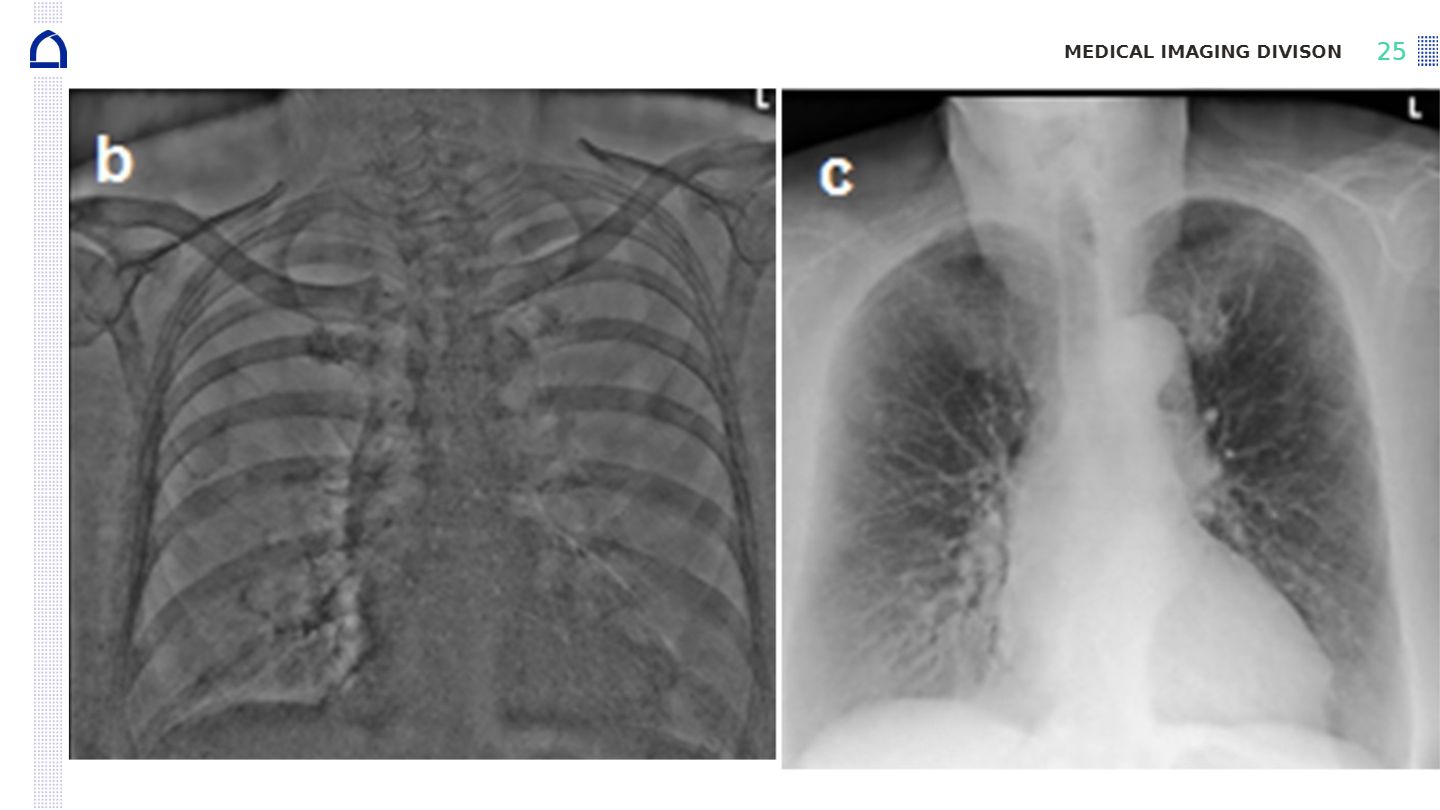

Compare the images shown after soft tissue removal and bone removal in dual energy subtraction. What differences can you observe and what clinical advantages do these differences provide?